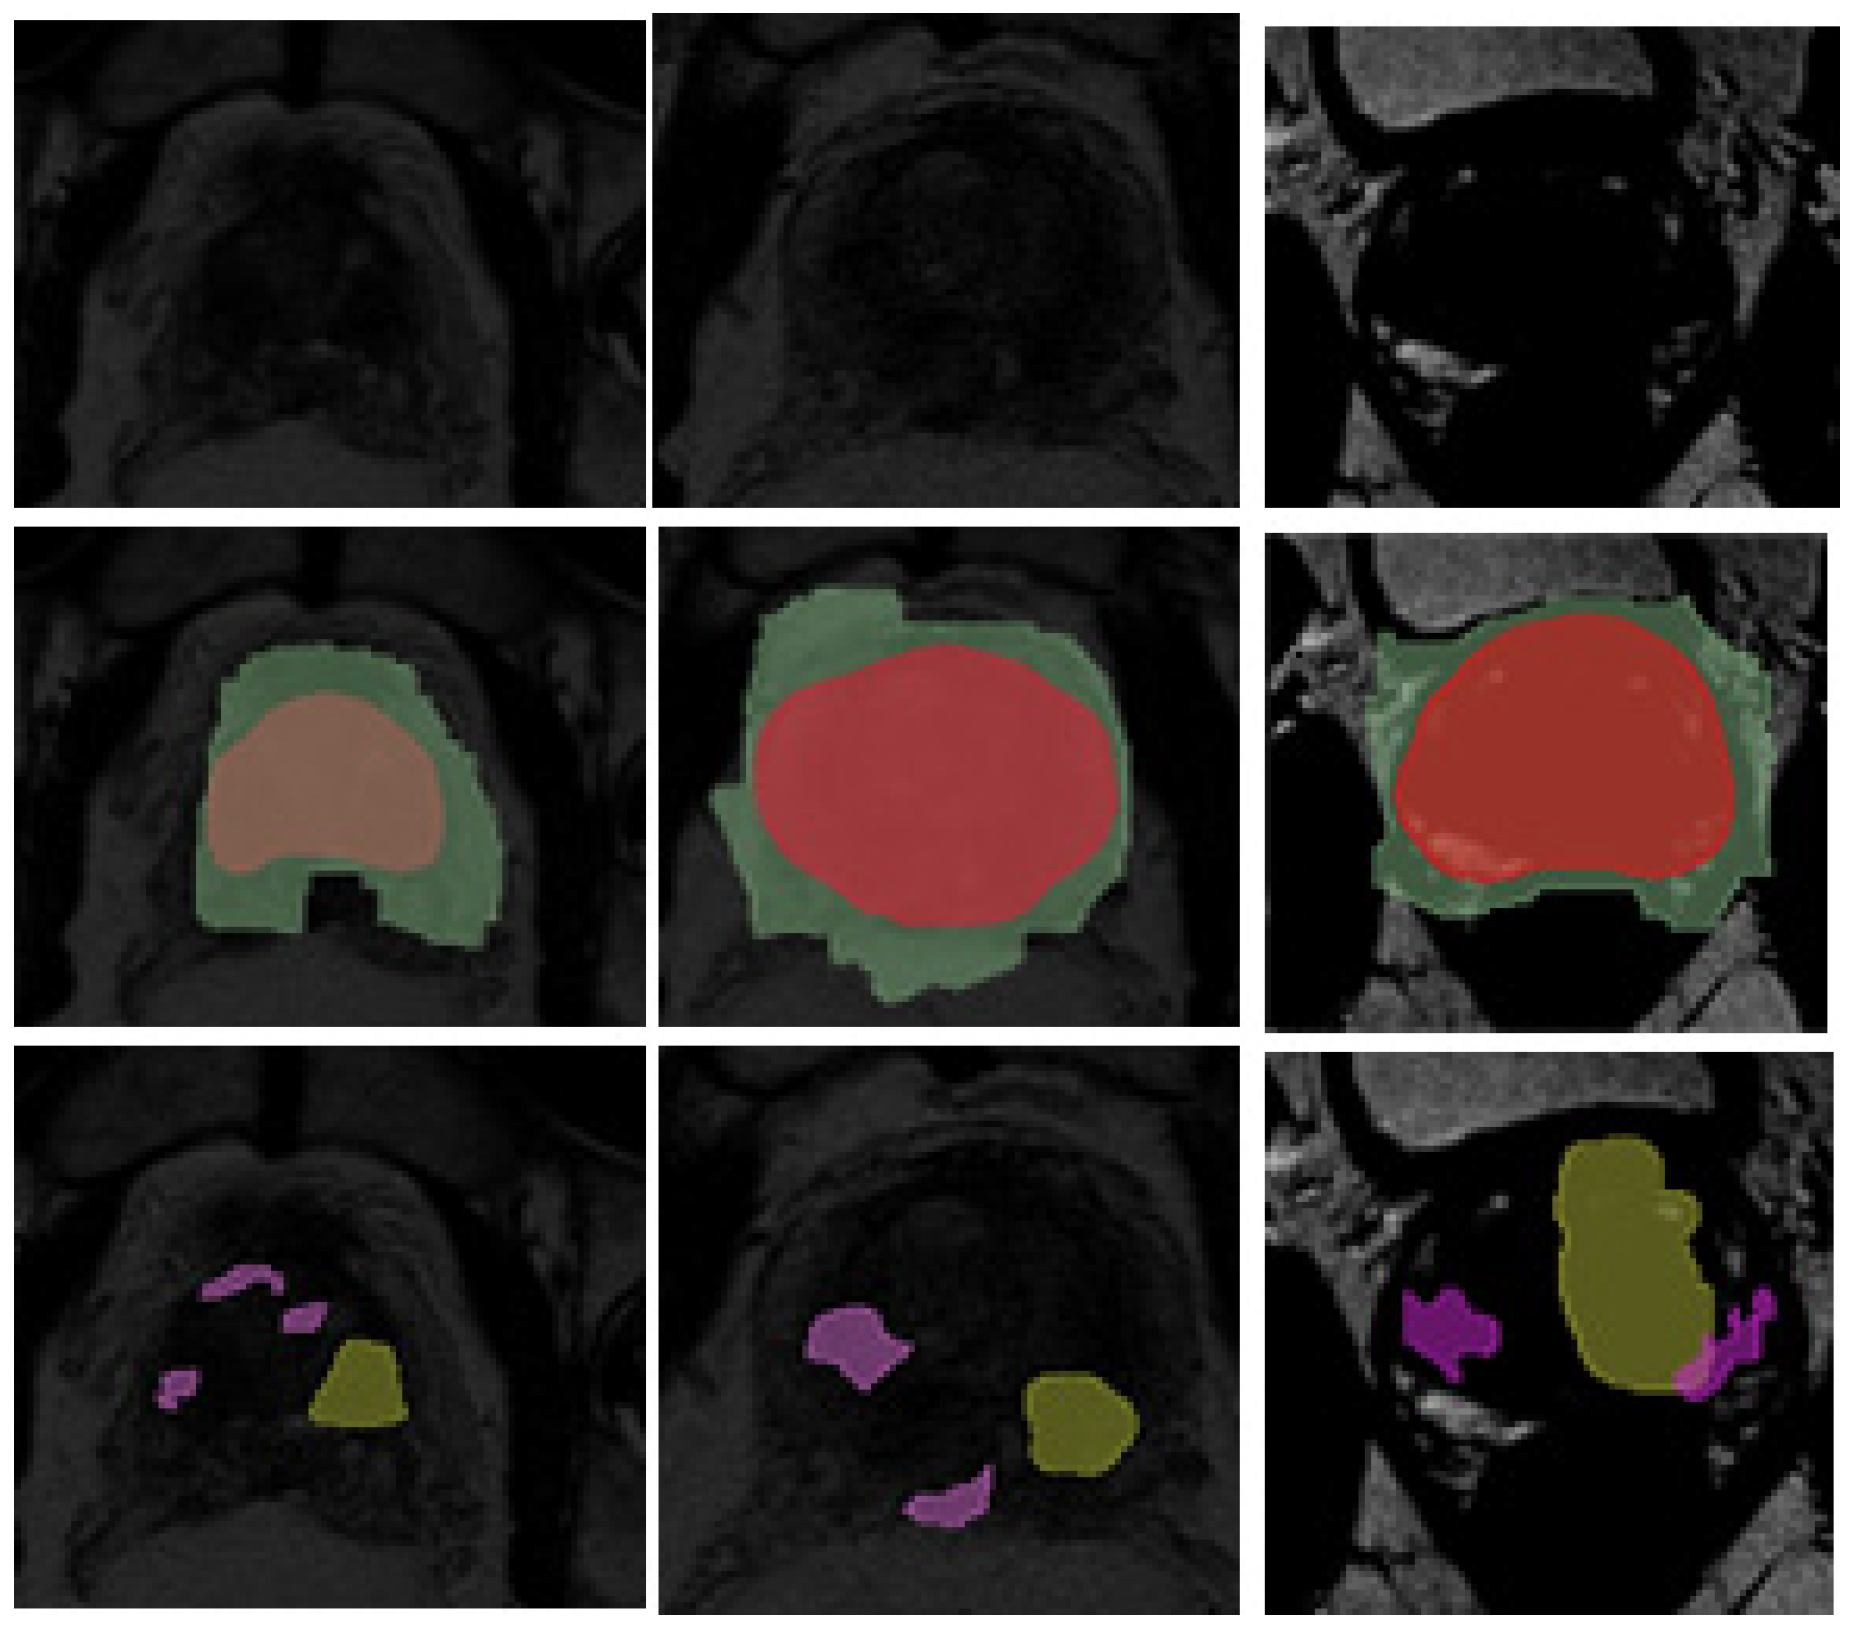

A potential bottleneck of this approach to segmentation is the loss of algorithmic flexibility in handling variable data. During our study, we encountered eight MRI scans that contained significant deviations in contrast values relative to the rest of the dataset. These scans produced the worst prostate and cancer segmentation results (Figure 19), even though prostate detection did not materially affect bounding-box localization. One of the future directions of our research will be to determine methods to address this issue.

Scans marked by contrast issues were obtained from a single medical institution. A brief review of these scans revealed that two tags (window width and window length) were omitted from the original DICOM files, which were used to generate the contrast ratio when displaying the scans. Since these tags were missing during DICOM conversion to NifTI format, this could be one of the reasons for the problematic data. This situation might have been caused by an error during scan generation or data anonymization. A practical solution to this problem is to verify the presence of these tags and substitute default values if they are missing.

A starting point for addressing this issue could be the use of an extended set of augmentation tools during data preprocessing. In our case, two options are possible: processing those eight scans only, such as by using external tools for automatic data contrasting, or increasing the dataset’s resilience to contrast outliers, such as by using augmentation tools to introduce random changes in brightness and contrast with high values of change probability and magnitude on the data used for training. In a specific case, manual adjustment of scans with contrast defects is possible by adjusting the WW and WL tag values in DICOM format (before conversion to NifTI format). However, this approach would be impractical, as contrast may depend, among other things, on the MRI machine settings. Such limitations necessitate addressing the issue through automated data processing or by increasing the model’s resilience to data variability.

Figure 19. Examples of scans with contrast outliers and segmentation errors.